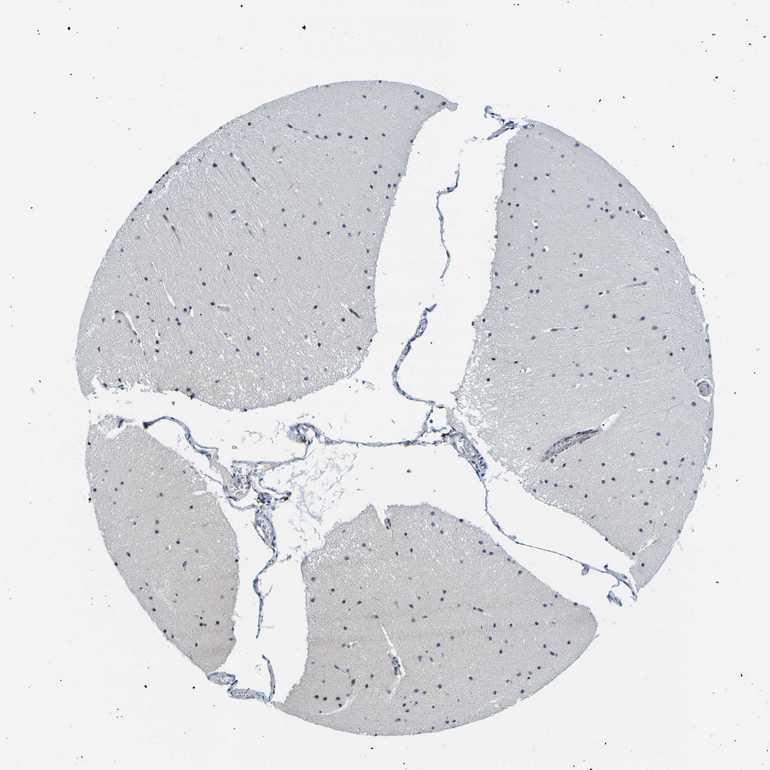

CEREBELLUM - Antibody stainingi

Antibody staining in the annotated cell types in the current human tissue is reported as not detected, low, medium, or high, based on conventional immunohistochemistry profiling in selected tissues. This score is based on the combination of the staining intensity and fraction of stained cells.

Each image is clickable and will lead to virtual microscopy that enables deeper exploration of all samples and also displays staining intensity scores, fraction scores and subcellular localization as well as patient and tissue information for each sample.

Antibody HPA018419Antibody HPA048790

Purkinje cells Not detectedNot detected

Cells in granular layer Not detectedNot detected

Cells in molecular layer Not detectedNot detected